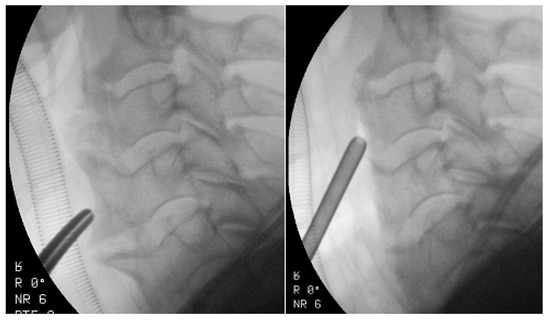

Surgical treatment involves the direct anterior removal of osteophytes (Figure 2) [62]. Surgical resection of osteophytes usually results in excellent symptom relief [53]. Spinal fusion may sometimes be warranted if there are accompanying symptoms of cervical-spine instability [63]. Spinal fusion should be considered in patients with concurrent spinal-cord or nerve compression, or spinal instability. Approximately 10% of patients with DISH associated dysphagia require surgical decompression, while 70–100% of patients report improvement in dysphagia after the surgical resection of anterior cervical-spine osteophytes [64]. Worse results were reported in older patients (>75 years) [61,64]. Large osteophytes increase the risk of damage to the esophagus during surgical exposure. The esophagus can be difficult to mobilize, and to some extent, adhere to other cervical fascia due to a local inflammatory response. The complication of the procedure concerns the esophagus and recurrent damage to the laryngeal nerve [65]. Reossification with the formation of new osteophytes may occur, and a second operation may be indicated [50]. DISH recurrence of the cervical spine may slowly and progressively develop, with an average rate of 1–2 mm/year [61,66].

Figure 2.

Intraoperative fluoroscopic imaging before and after osteophyte removal in a 72-year-old patient with DISH with dysphagia.